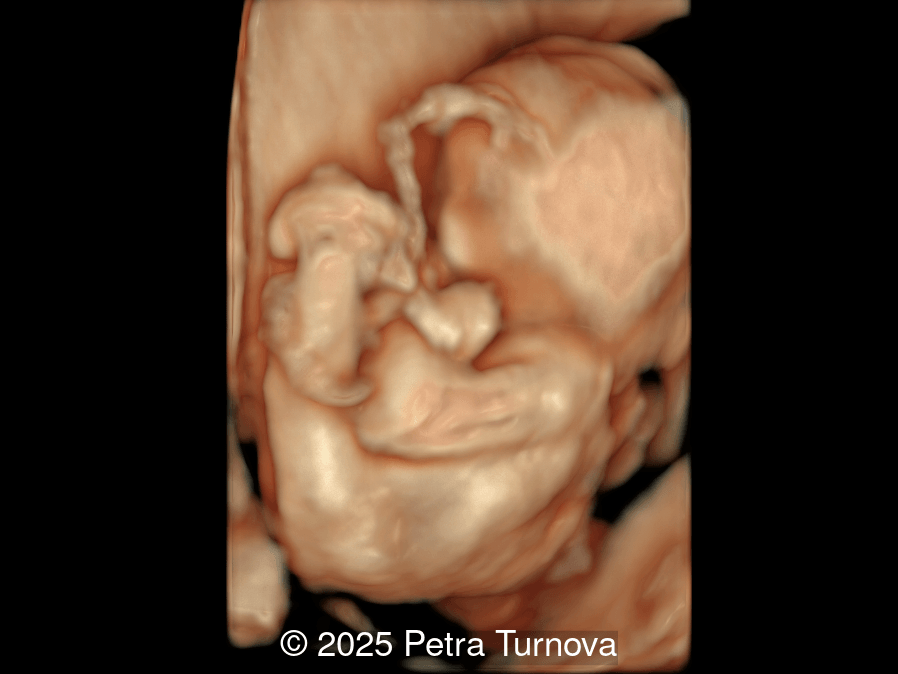

Our imaging revealed malformations in all four limbs with elbow, wrist, and knee joints fixed in extension, as well as foot and ankle malformations. Profile abnormalities were observed with prefrontal edema, flat profile and retro-micrognathia. Ultrasound demonstrated minimal stomach filling related to a lack of swallowing ability and hypoplastic lungs due to poor diaphragmatic movement. Nuchal edema was present.